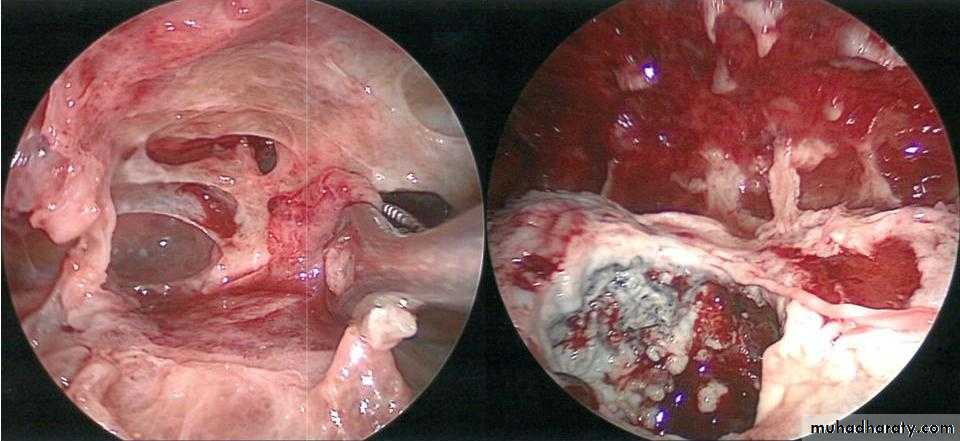

• 4-Bronchoscopy: To exclude intrabronchial tumor or foreign body

4- VATS or Thoracotomy : decortications with pleurectomy

• Bronchoscopy : To exclude or confirm Ca

• To diagnose and remove foreign bodies

• To drain an abscess

• To obtain a bronchial wash for C/S